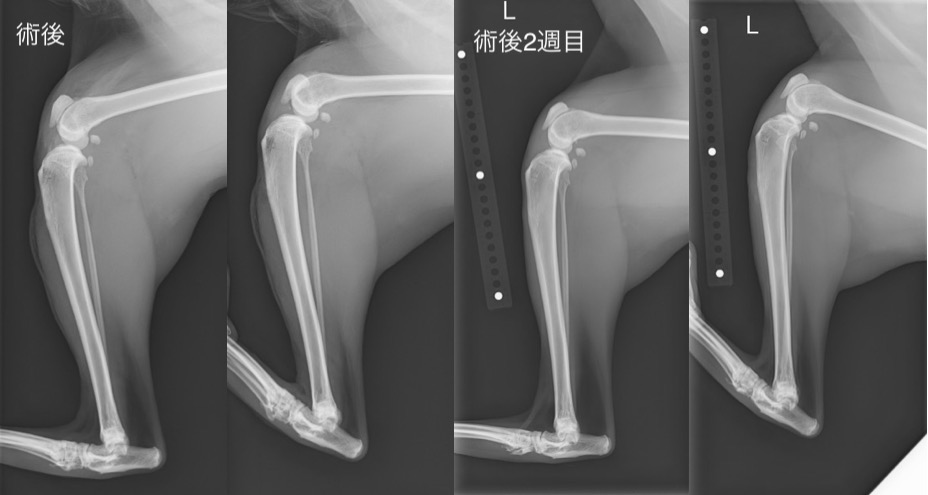

術後と術後2週目の比較(CrTTは認められず、まだ負重は弱いが、患肢も積極的に使うようになってきました。)